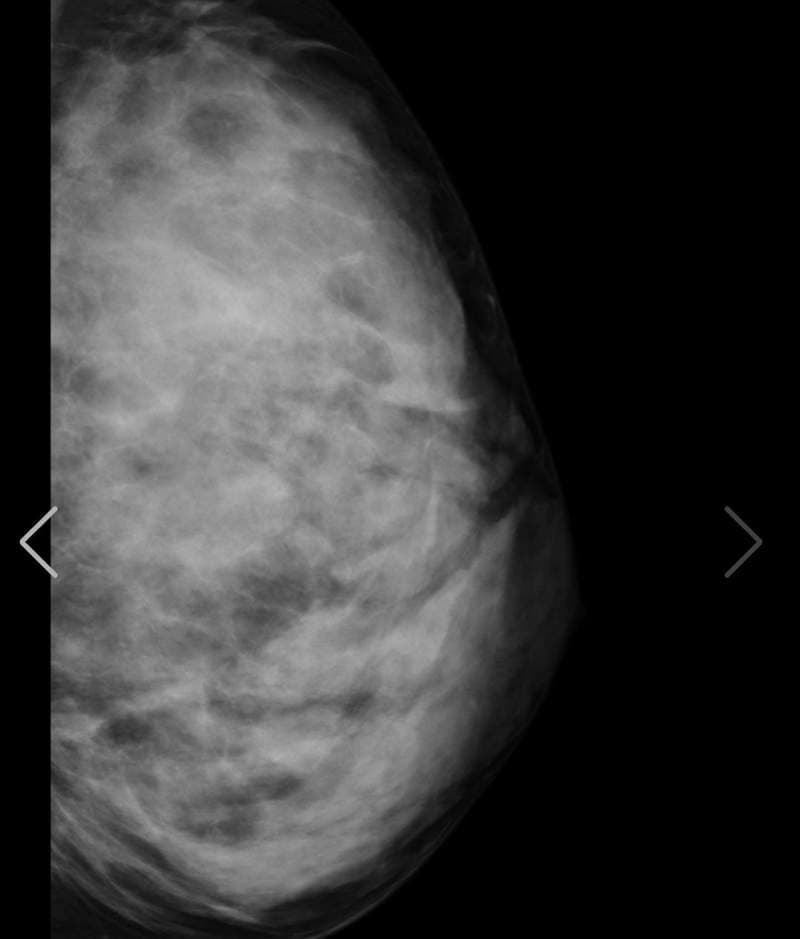

至于今天开头跟大家分享的上空X光照,大家千万不要觉得阿漆又要唬烂骗点阅,实际上她在最近真的有公开自己的X光照片,其实她在之前8月的时候曾确诊新冠肺炎,休养一个月之后康复已经完全健康,现在做个体检也是确认不要有后遗症

另外之前有网友曾质疑她胸部作假,这么大肯定不是天然的胸部,而这次在社群媒体上公开自己的体检结果,也间接打脸掉这个说法,她的胸部没有任何填充物,而右胸上小小的黑点是胃泡,所以整体检查结果下来是很OK的